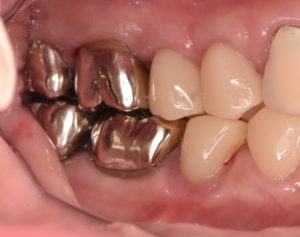

左上奥歯に不適合のクラウンとそれに伴う二次う蝕を認めた。レントゲン診査より根管治療の必要性も認めたため、再根管治療および再修復治療を行うこととした。その他全顎的に歯周炎を発症し、深いポケットを有する部分が多数存在した。

不良補綴物の除去

治療後